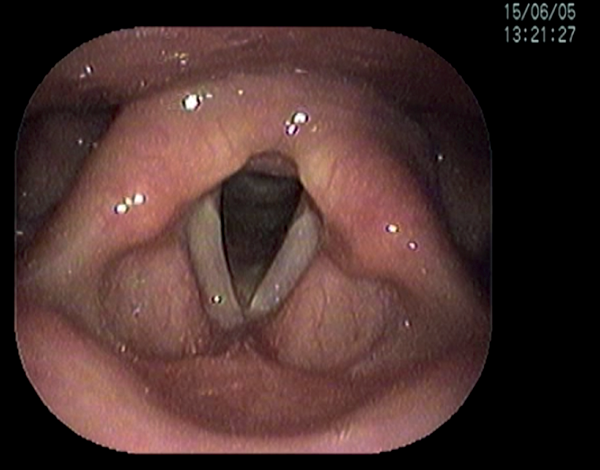

Short-term complications include perforation of the inner perichondrium and asymmetric laryngofissure. In the long-term, implant infection is rare. Hoarse voice or breathy voice can occur as well as recurrence of symptoms in about 10 % of cases. Revision surgery is rare. If it is required, this is usually due to breathy voice from a too wide titanium bridge. The long-term outcomes of this procedure are good. Figure 19 shows the vocal cords before and after surgery.

Figure 19: top 2 pictures) Before adduction, bottom 2 pictures) after adduction.